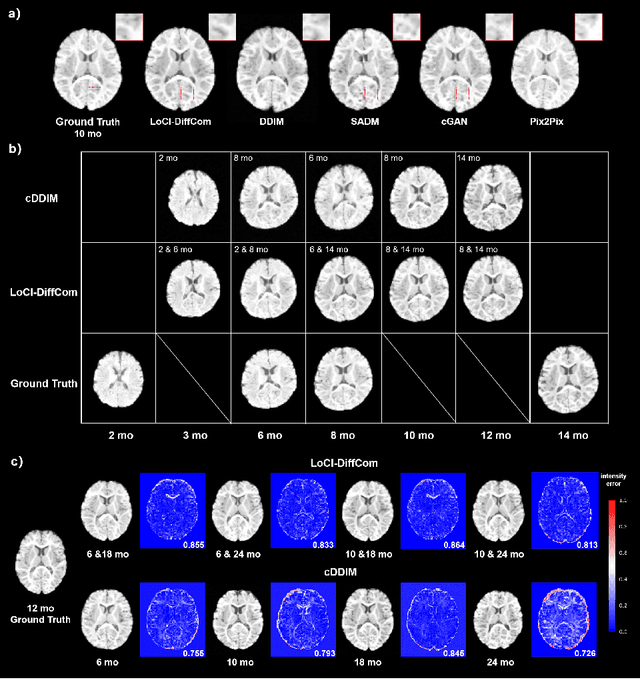

Abstract:The infant brain undergoes rapid development in the first few years after birth.Compared to cross-sectional studies, longitudinal studies can depict the trajectories of infants brain development with higher accuracy, statistical power and flexibility.However, the collection of infant longitudinal magnetic resonance (MR) data suffers a notorious dropout problem, resulting in incomplete datasets with missing time points. This limitation significantly impedes subsequent neuroscience and clinical modeling. Yet, existing deep generative models are facing difficulties in missing brain image completion, due to sparse data and the nonlinear, dramatic contrast/geometric variations in the developing brain. We propose LoCI-DiffCom, a novel Longitudinal Consistency-Informed Diffusion model for infant brain image Completion,which integrates the images from preceding and subsequent time points to guide a diffusion model for generating high-fidelity missing data. Our designed LoCI module can work on highly sparse sequences, relying solely on data from two temporal points. Despite wide separation and diversity between age time points, our approach can extract individualized developmental features while ensuring context-aware consistency. Our experiments on a large infant brain MR dataset demonstrate its effectiveness with consistent performance on missing infant brain MR completion even in big gap scenarios, aiding in better delineation of early developmental trajectories.